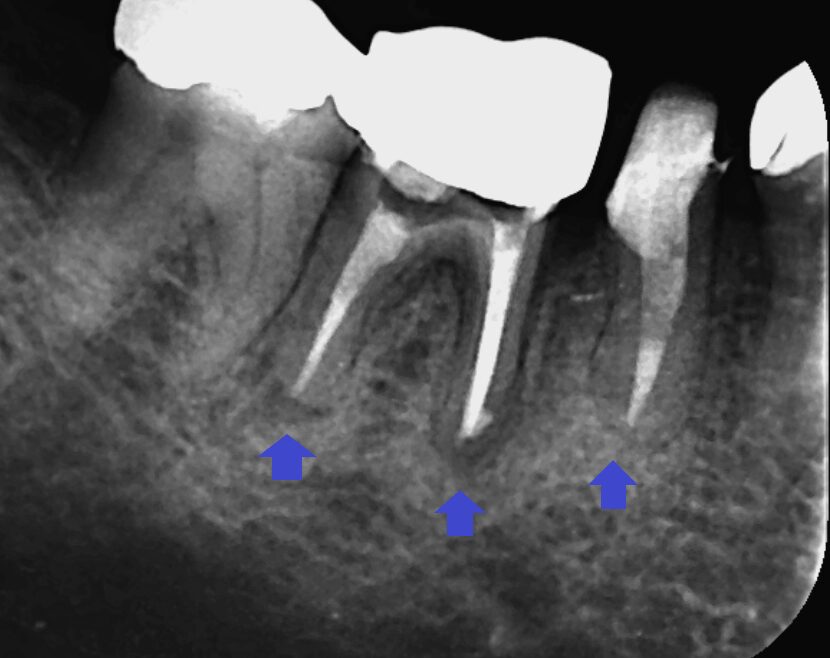

抜歯を避けるべく、精密根管治療を行いました。画像は根管充填のレントゲン写真です。第二小臼歯と第一大臼歯共に根の先までしっかり根管充填できました。